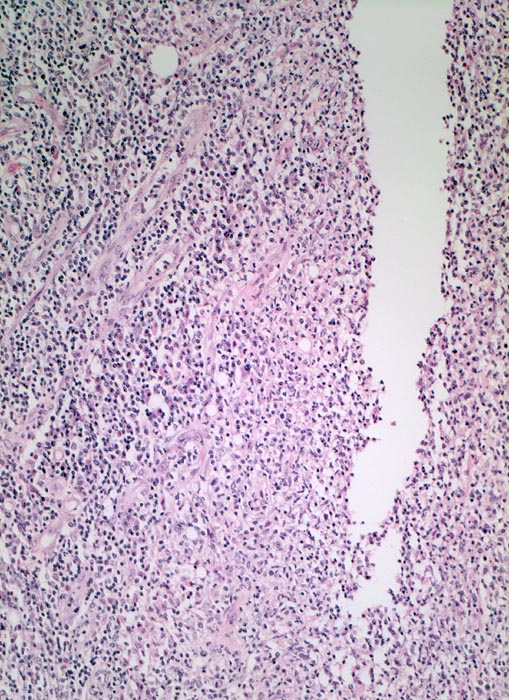

PathoPic ID 5087 - Morbus Crohn: fissurales Ulkus

Morbus Crohn: fissurales Ulkus

Entzündung / Reparatur

Ileum terminal

Darm, Anus

Spaltförmiges Ulkus gesäumt von entzündlich infiltriertem Granulationsgewebe mit zahlreichen

Gefässen.

Bekannter Morbus Crohn. Resektion des terminalen Ileum wegen mechanischem Subileus und enterokutaner Fistelbildung.

Die Vermehrung von Nerven ist typisch bei Morbus Crohn.

Vergrösserung

100